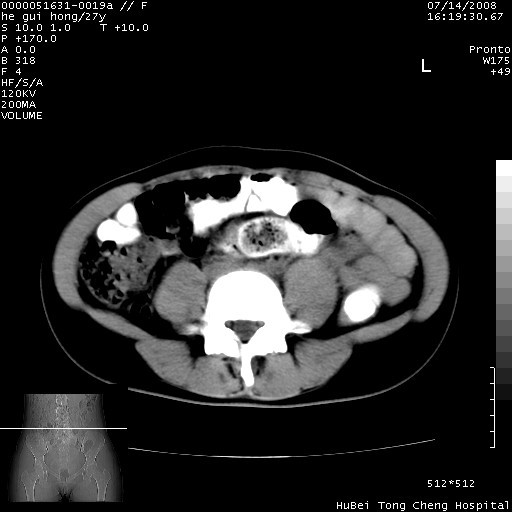

以下是引用杀毒软件在2008-7-20 8:03:00的发言:[br]支持双侧卵巢囊腺瘤可能性大!

以下是引用zjzjr在2008-7-20 13:36:00的发言:[br]双侧附件囊腺瘤可能性大!